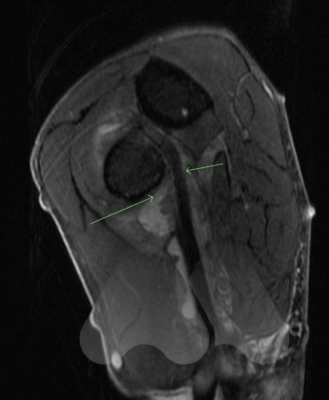

Acute distal biceps tears often occur in men over the age of 40 years of age due to a forced extension of a bent elbow, such as trying to catch a falling heavy object. Patients often feel a pop in the elbow accompanied by pain and bruising in the upper arm close to the elbow. A bunching of the muscle and loss of the normal muscle contour compared to the normal side can sometimes be seen. These symptoms occur due to the tear of the biceps tendon from the forearm bone of the radius as it attaches past the elbow. Contrary to popular belief, the biceps main role is to rotate the forearm and not to bend the elbow. If left untreated, the tendon can retract into the upper arm and cause persistent weakness in the arm such as using a screwdriver or hammer and early fatigue when carrying heavy loads. Research has shown the loss of strength of 25-40% for rotation of the forearm (supination) and only 12% loss of strength in elbow flexion.